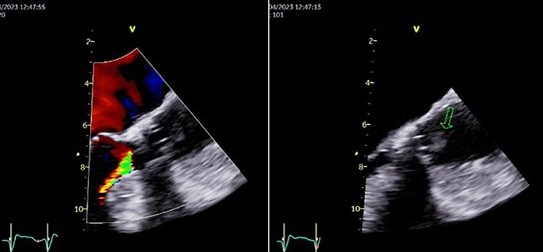

• Valvular Prosthesis Thrombosis Associated with DOACS: A Case Report

Juliana Carneiro, João Miguel Santos, Davide Moreira

164-167

DOI: https://doi.org/10.60591/crspmi.417